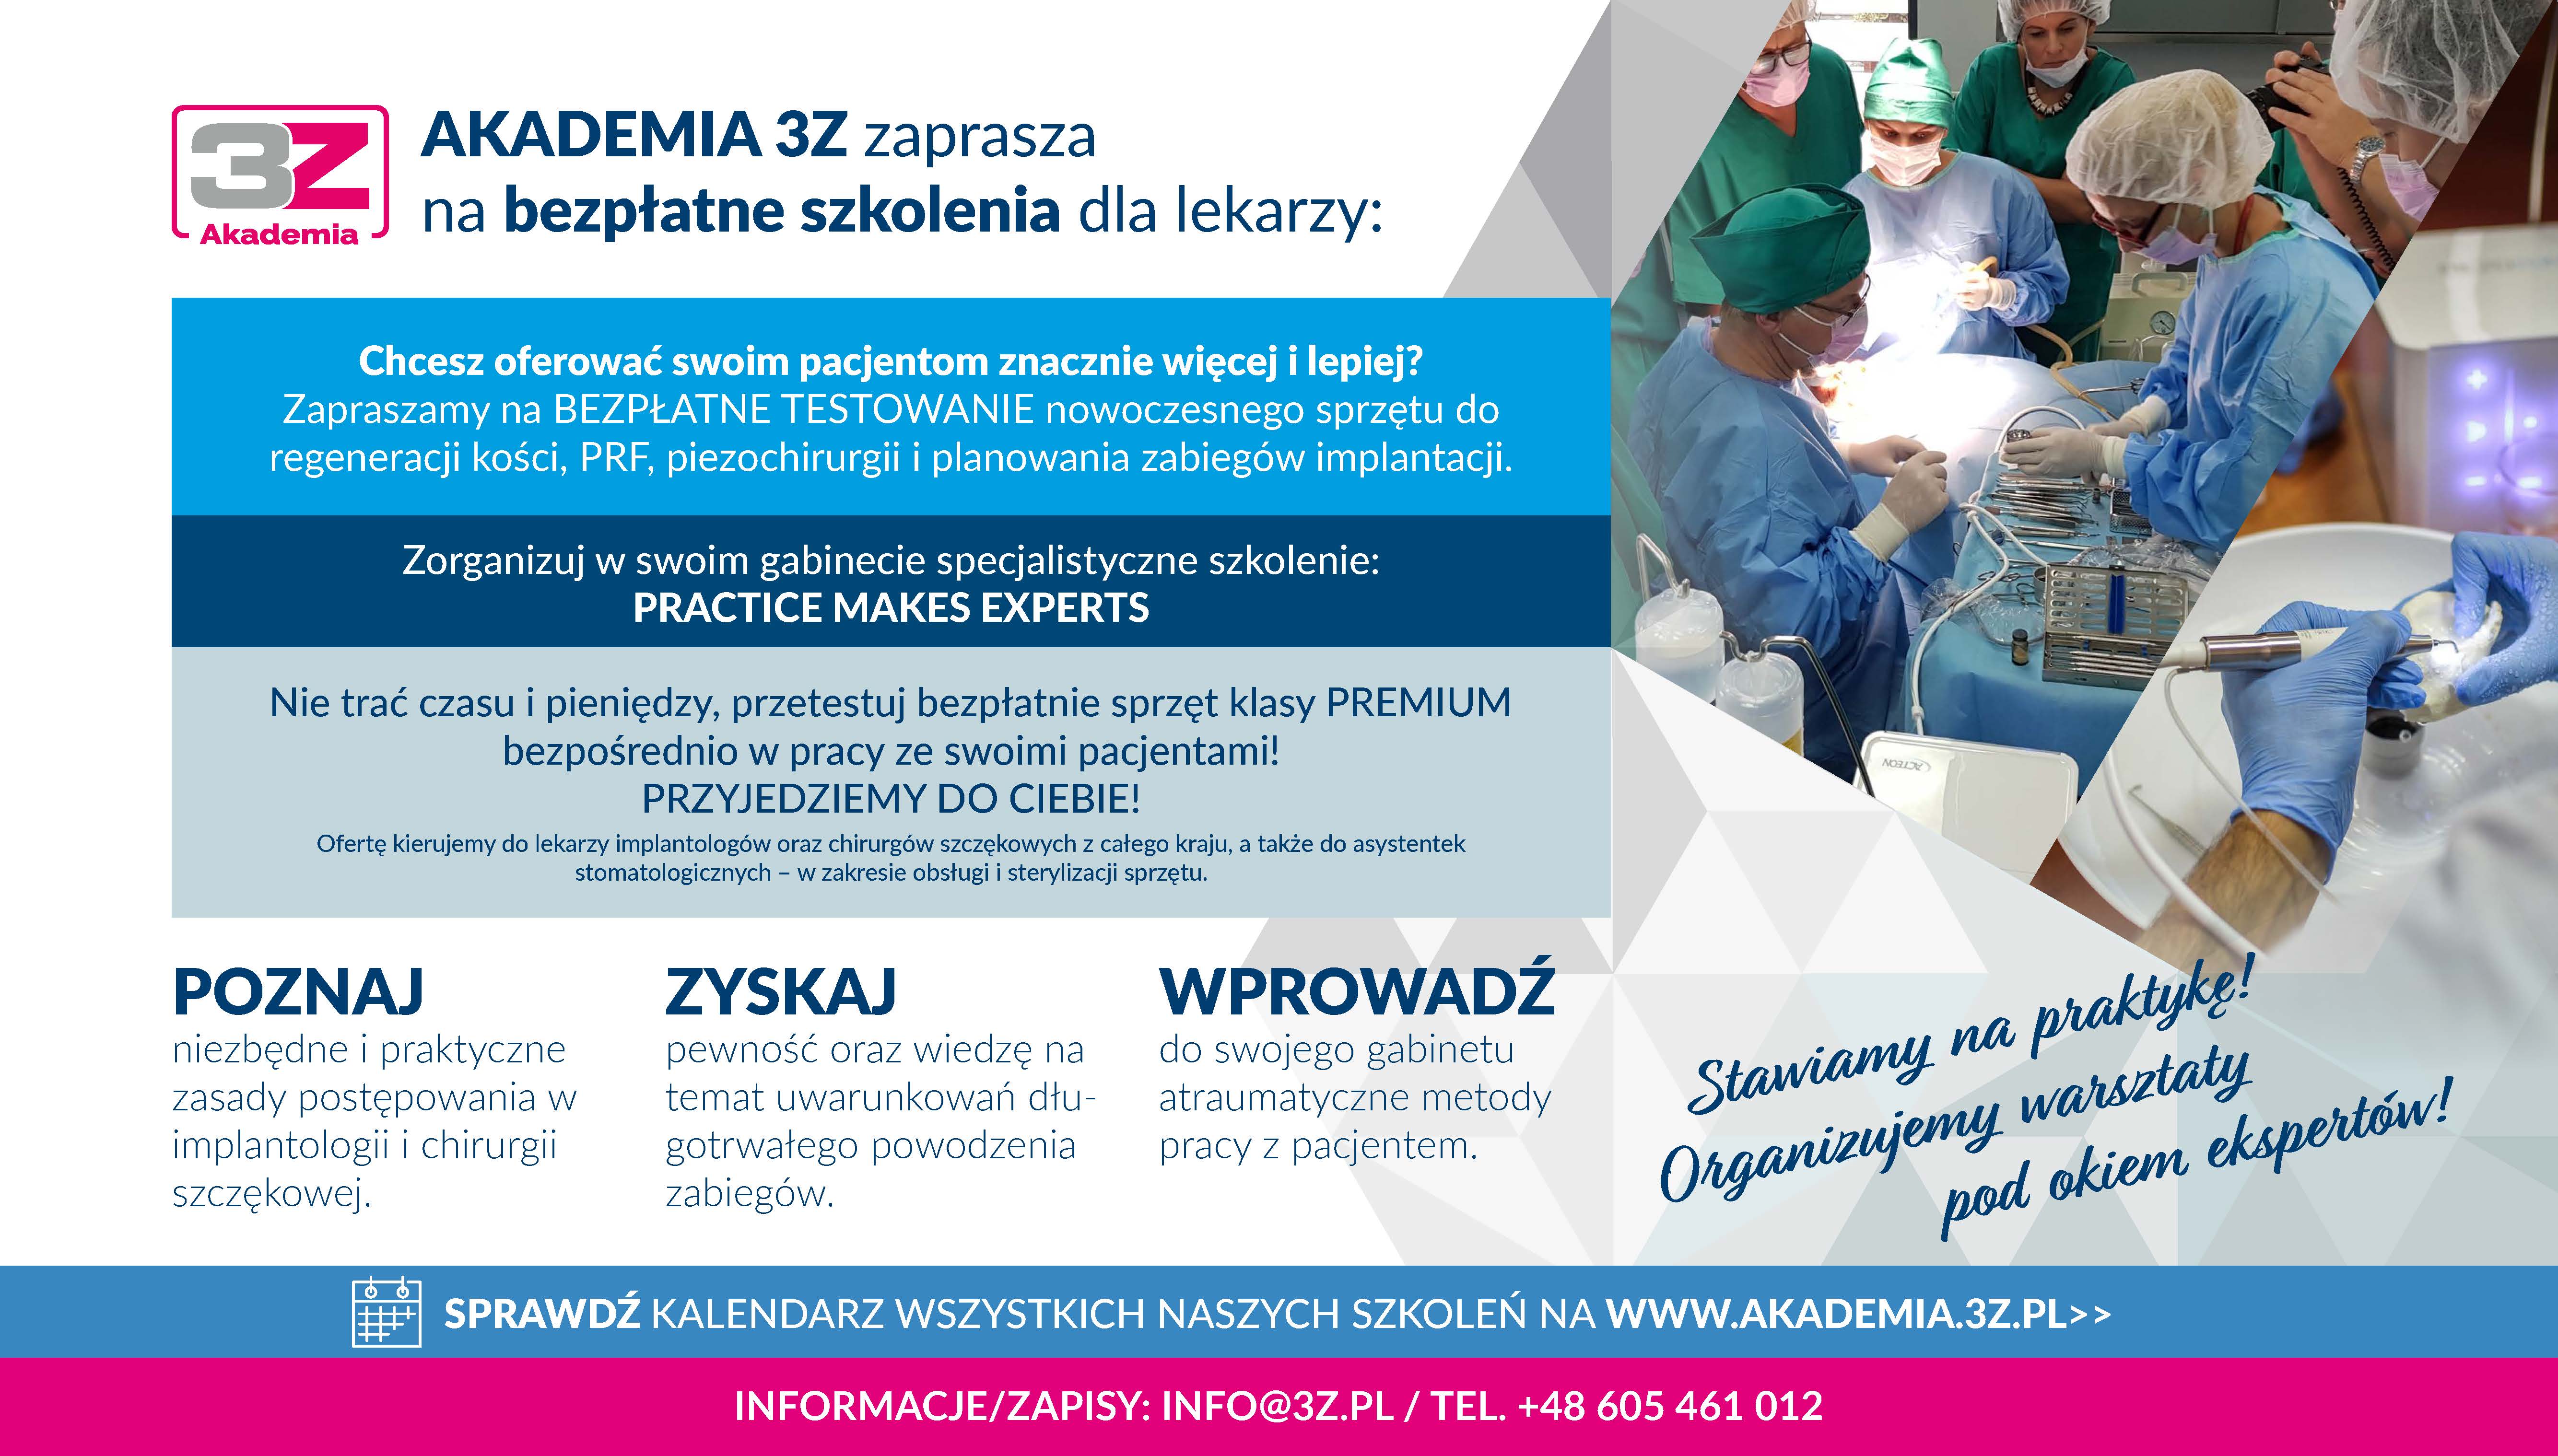

Szablony i wsparcie techniczne:

+48 697 301 765 / magellan@icx.com.pl